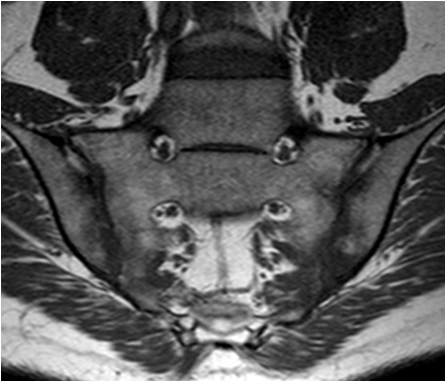

Ankylosing spondylitis affects synovial and cartilaginous joints as well as sites of tendon and ligament attachment to bone (entheses). An overwhelming predilection exists for involvement of the axial skeleton, especially the sacroiliac, apophyseal, discovertebral, and costovertebral articulations. Early in ankylosing spondylitis there is sacroiliac joint involvement with blurring of the joint margins and some reactive sclerosis. Then changes appear at the thoracolumbar and lumbosacral junctions.

Therefore, sacroiliitis is the hallmark of ankylosing spondylitis. Although an asymmetric or unilateral distribution can be evident on initial radiographic examination, roentgenographic changes at later stages of the disease are almost invariably bilateral and symmetric in distribution. This symmetric pattern is an important diagnostic clue in this disease and may permit it differentiation from other disorders that affect the sacroiliac articulation, such as RA, psoriasis, Reiter's syndrome, and infection. Changes in the SI joint occur in both the synovial and ligamentous (superior) portions, and predominate on the iliac side.

Inflammatory synovial changes and subchondral edema are well seen on MRI. MRI is more sensitive and is being used with increased frequency to detect and stage inflammatory nvolvement of the sacroiliac joint in patients with ankylosing spondylitis.

Fig. 16. T1 weighted and STIR images of the sacroiliac joints in a young patient with low back pain. Low signal areas on T1 correspond with edema seen on STIR. Note the joint space narrowing and the more pronounced subchondral changes in the iliac bone as compared to the sacrum.